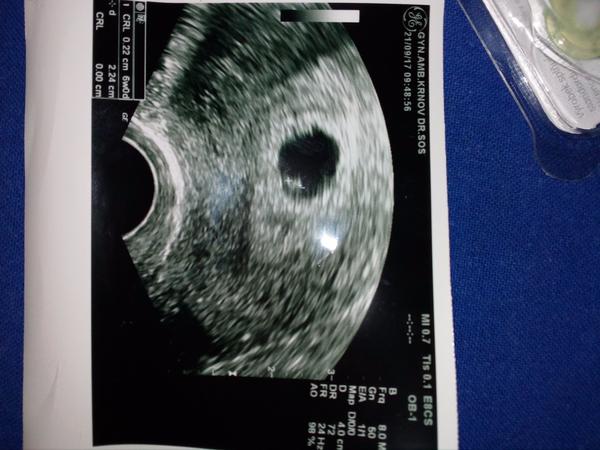

Tohle je ultrazvuk cca 6tt jak mi řekla že je vše v pořádku...